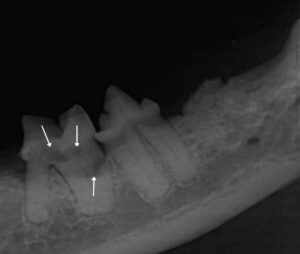

During the COHAT procedure, leons teeth were individually examined and charted, and full mouth X-rays were taken to assess his dental health comprehensively.

Visual examination and probing revealed significant tartar accumulation, gingival inflammation, and evidence of tooth resorption, particularly in the caudal teeth. The diagnosis of tooth resorption was confirmed with dental x-ray and extraction of these affected teeth was deemed necessary. Dental nerve blocks using bupivacaine at a dose of up to 1mg/kg were administered to ensure pain free extraction of these teeth.

Careful attention was paid to avoid complications such as root fractures or leaving behind any root fragments. Three affected teeth, on the right hand side of the mouth were successfully extracted during the initial COHAT, with plans for a second-stage procedure to address the remaining affected teeth on the left side of the mouth. By breaking down extensive dental procedures into manageable stages, we aim to minimise anaesthesia duration, aiming for a maximum time of 2 hours per procedure. This approach aims to mitigate the risks associated with prolonged anaesthesia, enhancing overall safety. Additionally, this strategy allows for one side of the mouth to heal before addressing the other.